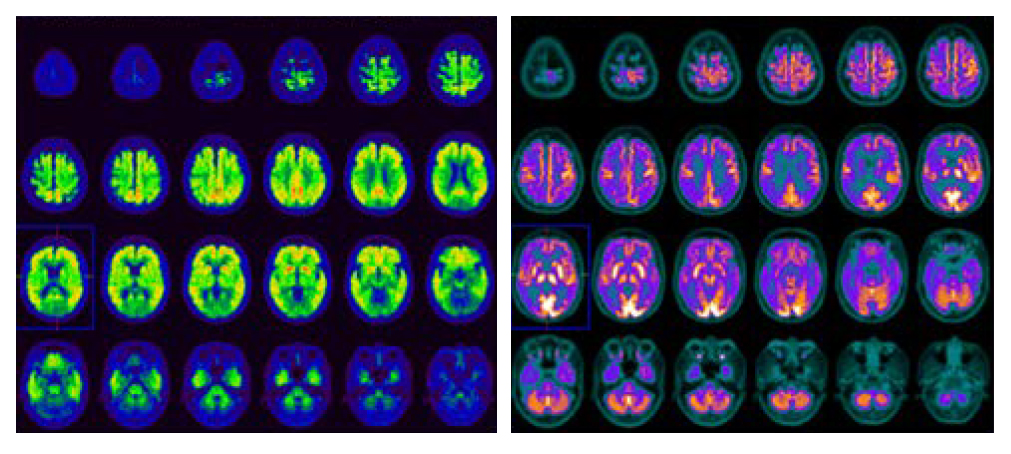

正電子/電腦雙融掃描和阿茲海默症

正電子掃描可以顯示和量度細胞及物質在腦內的活躍度及分佈。養和提供的正電子/電腦雙融掃描檢查利用多種的示蹤劑,能協助診斷阿茲海默症和其他導致認知障礙疾病的成因:

• 11炭-澱粉樣蛋白和18氟-Tau蛋白正電子/電腦雙融掃描可測量大腦中澱粉樣蛋白和Tau蛋白的異常累積,用以診斷阿茲海默症

• 18氟-脫氧葡萄糖正電子/電腦雙融掃描能測量大腦中的葡萄糖代謝,用以區分阿茲海默症和其他認知障礙疾病成因

正電子/電腦雙融掃描能有效地在出現病徵前偵測早期的阿茲海默症,預測及評估病情進展。腦神經科專科醫生便能協助病人早作準備,以減低日後出現認知衰退的影響。